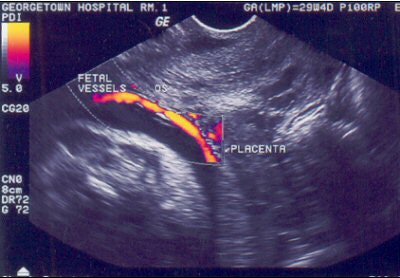

| Vasa previa can be diagnosed by transvaginal color Doppler ultrasound, as shown on this image. Image courtesy of the International Vasa Previa Foundation. |